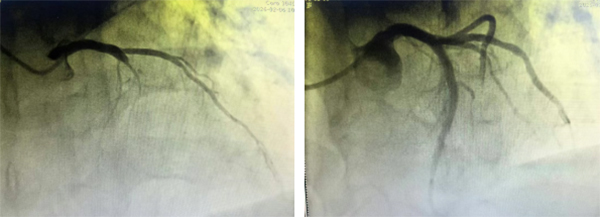

面对这一高难度、高风险的手术挑战,在北京大学滨海医院王宽心脏介入团队的帮助下,由左国兴主任、王蹿蹿主任及生态城医院内科等成员组成的心脏介入团队周密部署,凭借丰富的临床经验和精湛的操作技术,术中精准制定手术方案,采用“球囊支撑”等专业策略,在精细操作下成功将导丝通过坚硬迂曲的闭塞病变段,并精准植入支架,顺利开通患者闭塞的冠状动脉血管。术后造影显示,患者血管恢复畅通,血流达到理想水平,手术取得圆满成功。